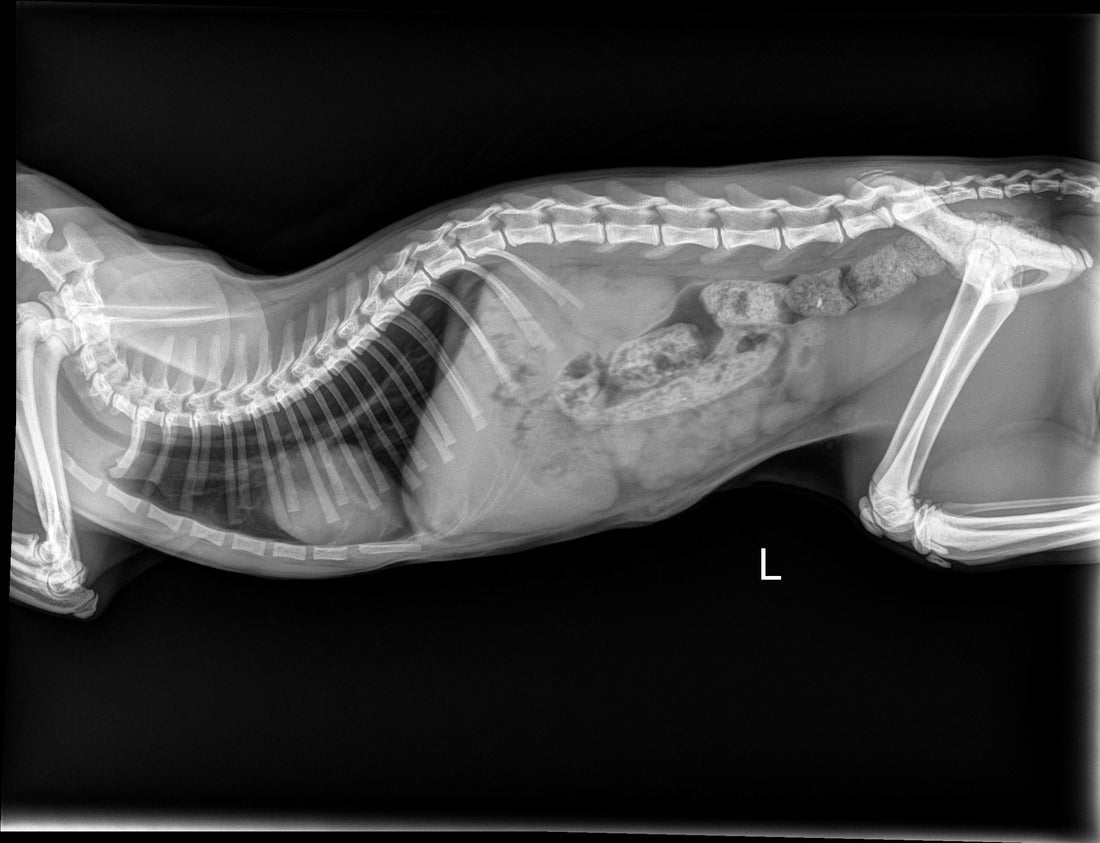

When we need to figure out what’s wrong with your pet, we routinely use x-rays to help identify the cause of the problem, rule out possible problems, or provide a list of possible causes. We may also use x-rays during a wellness exam to diagnose potential problems before they become serious.

X-rays provide valuable information about a pet’s bones, gastrointestinal tract (stomach, intestines, colon), respiratory tract (lungs), heart, and genitourinary system (bladder, prostate). We use radiology alone or in conjunction with other diagnostic tools. Interpretation of radiographs requires great skill on the part of the veterinarian.

We offer digital radiology (x-rays that are captured digitally rather than on film). This technology allows us to provide you with a quicker diagnosis for your pet. Plus, it uses less radiation than traditional x-rays.